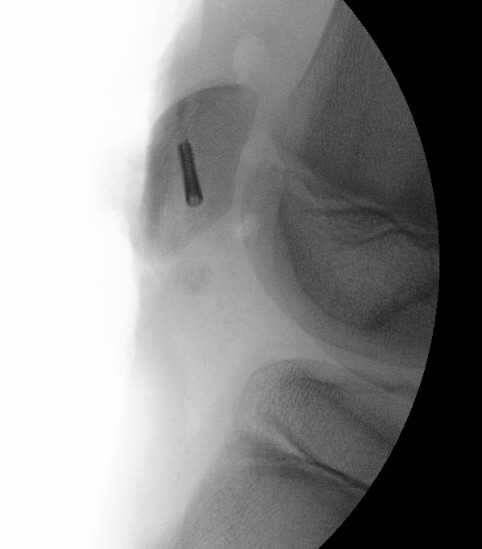

Technique

Depends on size of fragment

- intra-osseous sutures

- tension band wires

- suture anchors

Fixation of osteochondral fragment with headless compression screws, and sleeve fixation with sutures anchors

Patella sleeve ORIF with tension band wires